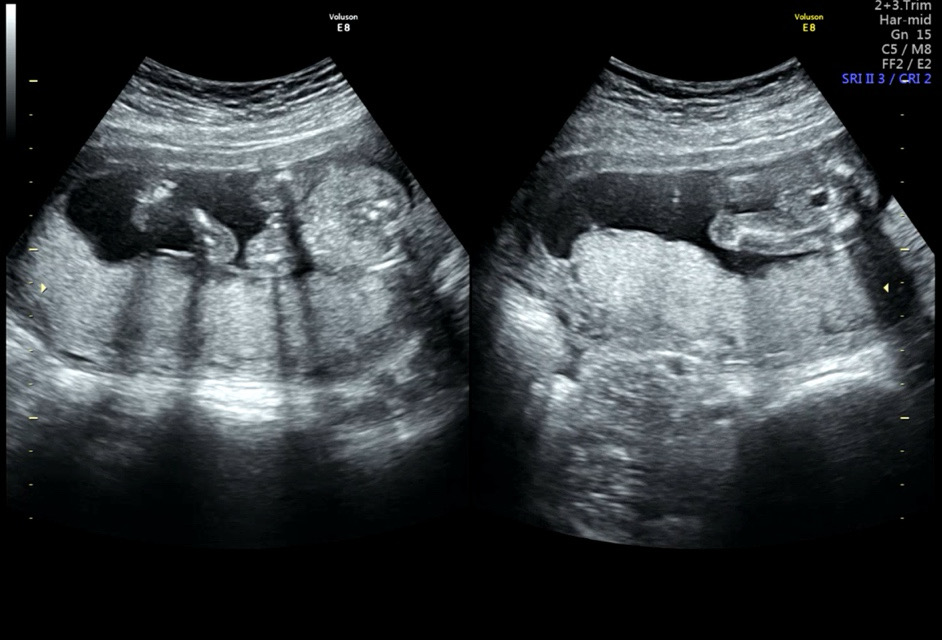

16주 6일 아들,,? 딸,,?! 궁금해요 도와주세요

궁금해 미치겠어용 ..! 원장님두 시원하게 말씀을 안해주시고 애매하시다며 반전이 있을 수 있다셔서 ㅜㅠㅠ 기다려야함을 알지만서도,, 궁금함을 견딜수가 없네요

탈퇴한 유저

아들이네요ㅋ 16주면 확정이예요~축하드려요

아들인데 사진에 고추가 좀 작게 나왔네요